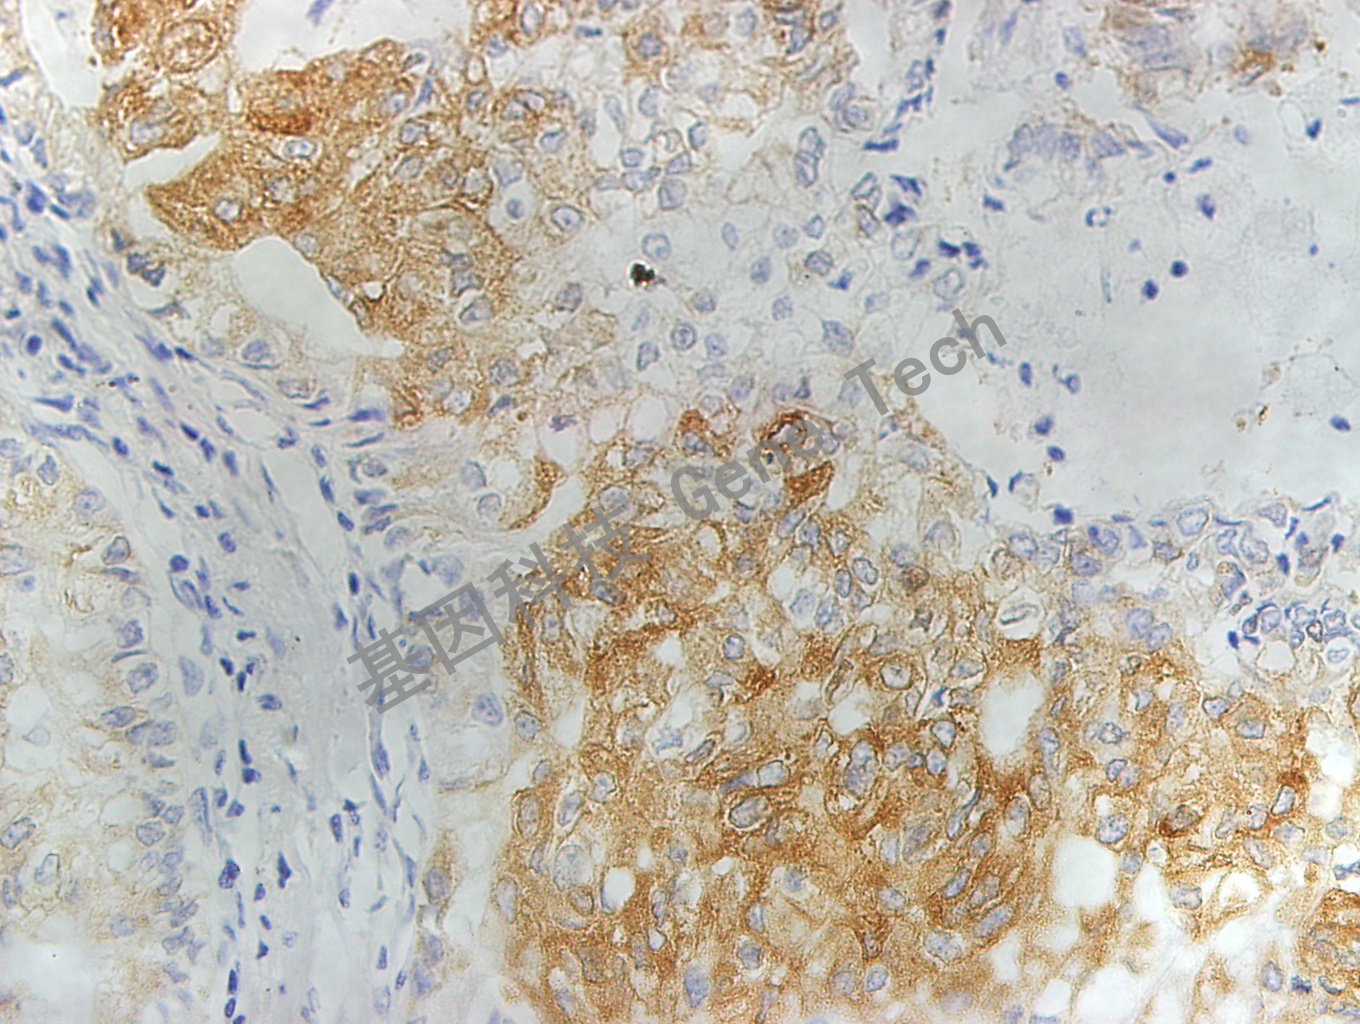

| 預處理:高pH熱修復 | 陽性部位:細胞漿 | 陽性對照:乳腺癌 |

| 肺石蠟切片,用 MRP1(GT2015)染色,細胞漿陽性,DAB 顯色 | ||